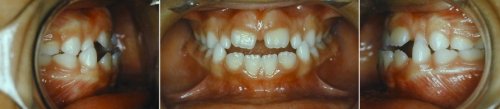

bmh orthodontie fonctionnelle chez l_enfant 2